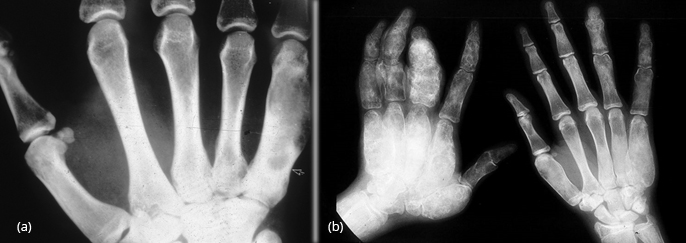

Figure 14: FD – (a, b) Radius, (c, d) Ulna In the hands, monostotic is rare.

Polyostotic is common with asymmetrical bilateral changes with mixed densities are encountered (Figure 15a,b).

Figure 15: FD – (a) Monostotic involving 5th metacarpal, (b) Polyostotic bilateral involving phalanges and metacarpals.

Not surprisingly bone affected by fibrous dysplasia is weaker than normal and thus susceptible to pathological fractures. Occasionally, rickets in children and osteomalacia in adults in encountered with fibrous dysplasia due to unknown humoral mechanism (Figure 28a,b).

Figure 28: (a) FD of proximal tibia with rachitic changes with increased distance between metaphysis and epiphysis of tibia, (b) FD metacarpals with rachitic changes, cupping of the radius and ulna of the wrist in a 7 yr old boy.